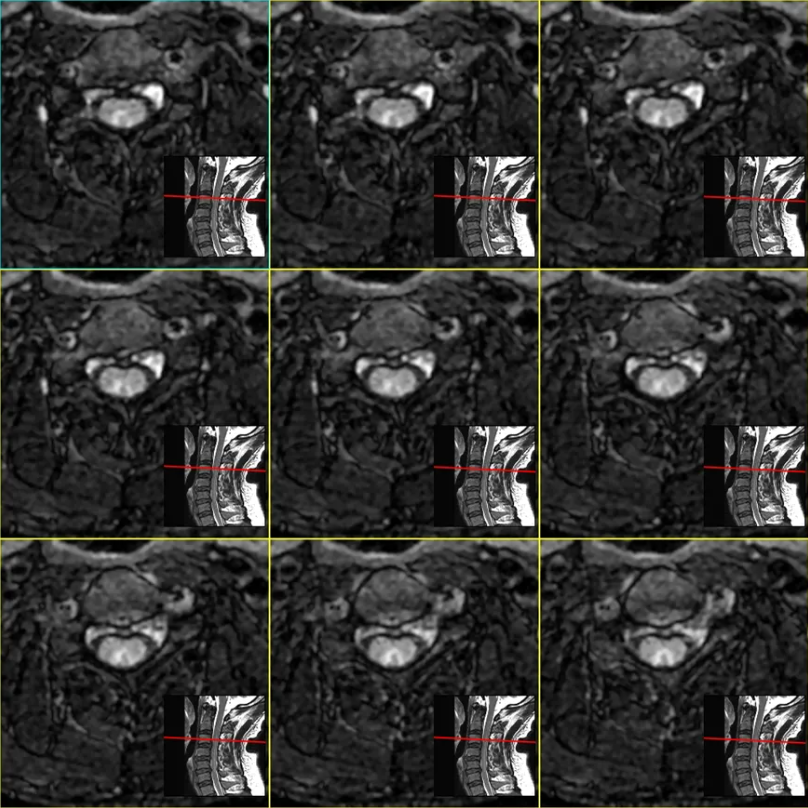

重建效果图:

五、综合诊断 脊髓亚急性联合变性(SCD) v由于维生素B12的摄入、吸收、结合、转运或代谢障碍导致体内含量不足而引起的中枢和周围神经系统变性的疾病。 v主要累及脊髓后索、侧索及周围神经,影像表现为倒置的“V”。 追问病史,该患者有长期大量饮酒史,胃功能受损